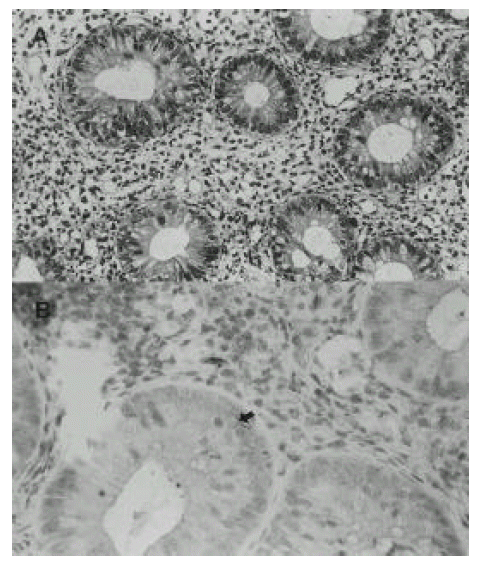

2. Histology and immunohistochemical staining of p53 protein

Among 16 UC patients, two patients (2%) with mild inflammation on colonoscopy showed low grade dysplasia on H&E stain. In addition, there were 4 patients who showed p53 overexpression in immunohistochemical stain (Fig. 1) and all of them were also shown to be positive for p53 mutation.

Fig. 1.

A: The lining epithelium of intestinal gland show low-grade dysplasia. (H&E, x400) B: The arrow shows positive immunohistochemical staining with p53 antibody.